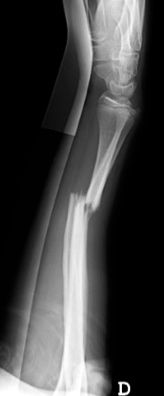

Las fracturas de ambos huesos del antebrazo al mismo nivel, con líneas de fractura oblicua-transversa o desplazamiento convergente son inestables y precisarán de tratamiento quirúrgico. En estos casos está indicado, dependiendo de la edad del paciente, el tratamiento mediante reducción y osteosíntesis. El enclavado intramedular elástico es el tratamiento de elección (Figura 15).

Figura 15: a-Imagen clínica de fractura de antebrazo derecho con gran deformidad. b- Radiografía donde se aprecia fractura de radio-cúbito de trazo transverso en el mismo nivel. c, d-Enclavado intramedular elástico. e,f- Imagen final con buena consolidación ósea.